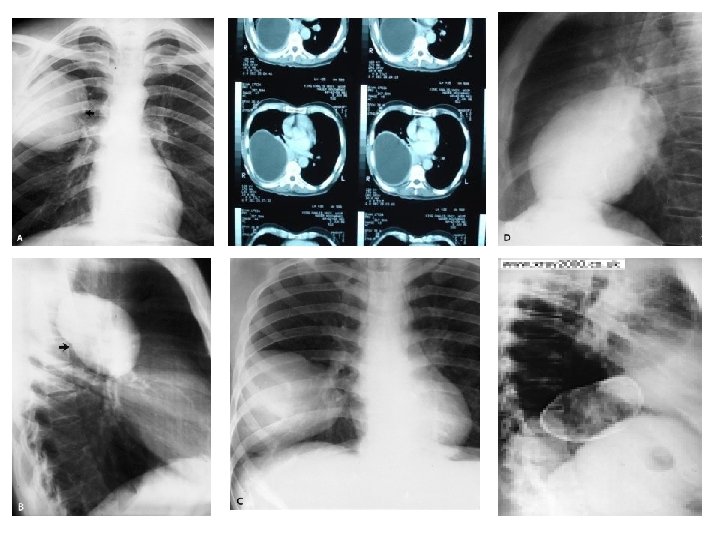

Left bronchus syndrome , Next slide Plzzz =) Notice , the Trachea is pulled to left side. . WHY ? cuz of fibrosis there is loss of space , loss of ventilation in the left side , the left lung is smaller in size , infective , bronchioectatic , it will pull the trachea toward it.

Left bronchus syndrome : Chronic condition , it is the end sequelae ﺍﻟﻨﺘﻴﺠﺔ ﺍﻟﻨﻬﺎﺋﻴﺔ of lung destruction due to TB In the previous slide , notice the bronchioectatic changes all over the lung ! Rt lung : pt still can breath from it , although it has apical scarring , Rt upper zone infiltration. Lt Lung : has Abcess cavity , Air Fluid levels , cystic bronchiectasis. If we did bronchoscopy , bronchoalveolar lavage , we will see the Fast Bacilli of Mycobacterium TB , which are resistant to 1 st , 2 nd and 3 rd line anti-TB medications ! ﻧﺘﻴﺠﺔ ﺑﺆﺮﺓ ﺍﻟﺘﻬﺎﺑﻴﺔ Left bronchus syndrome : The study was done at KKUH , if u r interested : http: //www. ncbi. nlm. nih. gov/pmc/articles/PMC 462386/pdf/thorax 00339 -0050. pdf 0

CT scan : infiltration , abcess formation , Lymph node